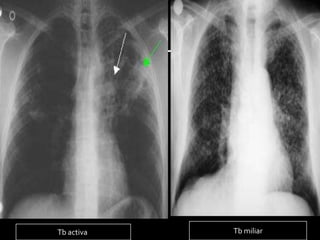

   Los hallazgos más frecuentes en la

tuberculosis primaria son las adenopatías y

las condensaciones

   La postprimaria las consolidaciones, los

nódulos y las cavidades, predominantes en

los segmentos apicales y posteriores de los

lóbulos superiores

Tb activa   Tb miliar